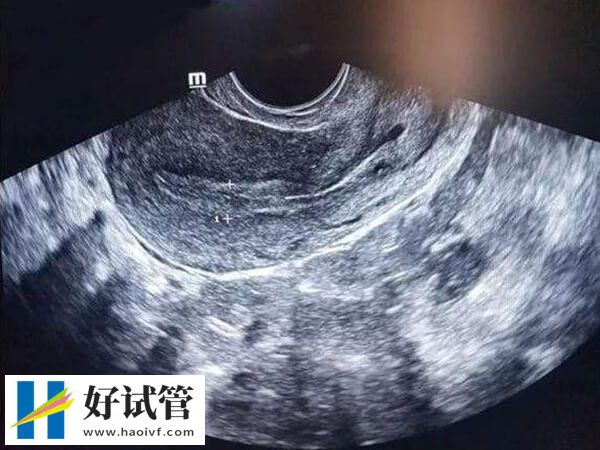

试管移植前内膜什么形态好

由于胚胎是在子宫内膜上着床的,所以在试管移植前,医生会反复检查女性的子宫内膜状态,只有符合标准了才会同意移植。而临床上将内膜分为了a、b、c三个等级,那么内膜abc哪个更容易着床,对此感兴趣的患者可以参考下列内容:

a型内膜出现在卵泡中期,此时,随着雌激素的不断刺激,子宫内膜逐渐增厚,大约在八毫米,构成三线征a型。如果这时子宫内膜厚度在8-12mm左右,那么此时移植后的受孕几率较大,移植成功率有明显提高。

B型内膜厚度在9-12mm之间,这种类型的内膜含有丰富的血管,雌激素水平较高,标志着接近排卵期,因此更适合胚胎着床。一般B型子宫内膜对于冷冻胚胎移植的妊娠率是比较高的。

C型内膜厚度在10-14mm之间,通常出现在排卵后黄体期,这个时期的内膜虽然厚度适中,但由于其分泌期的特性,可能不利于胚胎的着床。不过对于这种情况,可以通过药物治疗或其他医疗手段来调整,以达到更适合移植的状态。